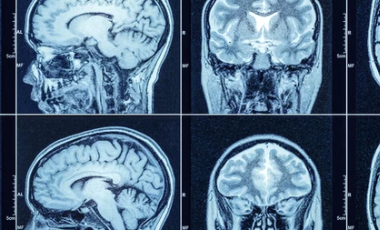

MRI(자기공명영상촬영)는 몸속 장기나 관절, 뇌, 척추 등을 정밀하게 확인할 수 있는 진단 장비입니다. 단순 엑스레이나 CT보다 정확한 진단이 가능하지만, 검사 비용이 높고 병원마다 가격 차이도 커서 부담스럽게 느껴지는 경우가 많죠.

MRI는 강력한 자기장을 이용해 인체 내부 조직의 구조를 고해상도로 촬영하는 영상 진단입니다.

방사선을 사용하지 않으면서도 뇌, 척추, 관절, 근육, 장기까지 폭넓게 진단 가능하다는 점에서 의학적으로 매우 중요한 검사입니다.